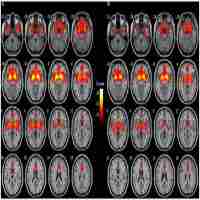

| Description | Journal: Alzheimer's & Dementia Both neurodegeneration of the cholinergic basal forebrain (BF) and deposition of β-amyloid are early events in the course of Alzheimer's disease (AD). Associations between increased amyloid pathology and cholinergic atrophy have been described in autopsy studies. We used structural MRI and AV45-PET amyloid imaging data of 225 cognitively normal or mildly impaired elderly subjects from the Alzheimer's Disease Neuroimaging Initiative to assess in vivo associations between BF atrophy and cortical amyloid deposition. Associations were examined using region-of-interest (ROI) and voxel-based approaches with reference to cytoarchitectonic mappings of the cholinergic BF nuclei. ROI- and voxel-based approaches yielded complementary evidence for an association between BF volume and cortical amyloid deposition in presymptomatic and predementia stages of AD, irrespective of age, gender, and APOE genotype. The observed correlations between BF atrophy and cortical amyloid load likely reflect associations between cholinergic degeneration and amyloid pathology as reported in neuropathologic examination studies. |